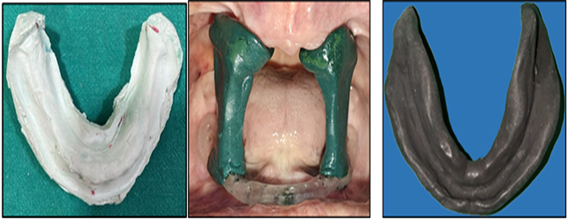

Figure 10: Mandibular Primary Cast, Stock Tray with Vertical Pillar & Secondary Impression using Cocktail Technique.

Edentulous Mandibular Impression

The primary cast was made using previous denture with alginate. The custom tray is fabricated using auto polymerizing acrylic resin. The special tray is made with 1mm spacer and cylindrical mandibular rest in posterior region are made at increased vertical height. High-fusing green stick compound was softened and placed on top of the mandibular rest and inserted in the patient’s mouth. The patient was advised to close her mouth. Adjustments were made so that the mandibular rest fit against the maxillary alveolar ridge properly. For final impression the wax spacer was removed, the impression compound and green stick compound in a 3:7 ratio was placed in water

at about 60°C and kneaded to a homogeneous mass and guided to close the mouth in rest. For recording the functional state, the patient is instructed to run his tongue along his lips, suck in cheeks, pull in her lips and swallow by keeping the mouth closed.